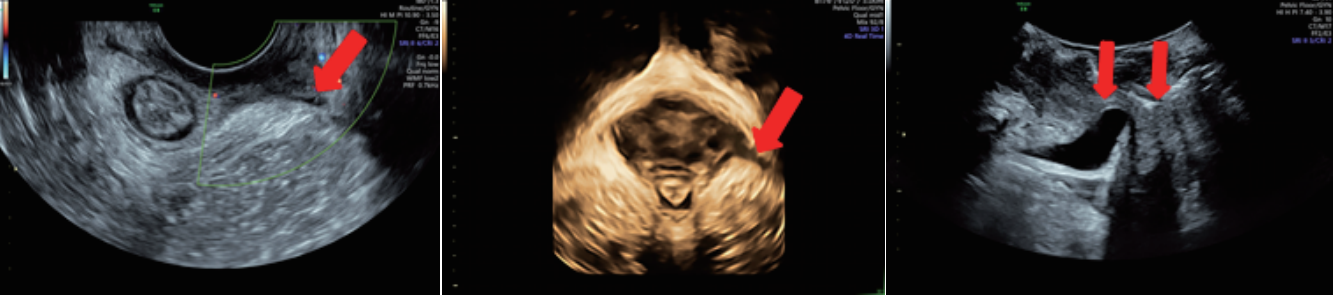

女性產(chǎn)后盆底功能檢查

輸卵管